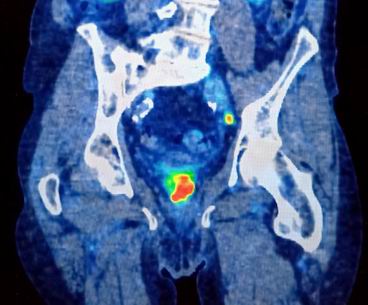

On 25/5/23 on a lovely sunny morning I cycled to the Churchill for the PET scan. They give you a radioactive injection and ask you to isolate from others for a half hour before the scan. Unlike MRI, PET scans are quite quiet and took around 20 minutes. The result shown on the right shows my prostate with the big red signal and the little red and yellow dot North-East is my metastatic pelvic lympth node. The strong signal from the prostate meant the a second radiotherapy was not an option. I had "advanced" metastatic prostate cancer.